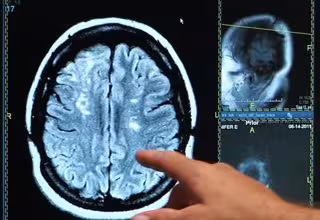

Un estudio describe cómo un derrame cerebral puede conducir a la pérdida permanente de la visión

Ictus, derrame cerebral, cerebro

Una nueva investigación de la Carnegie Mellon University (Estados Unidos) ha descrito con mayor precisión cómo el daño cerebral causado por un derrame cerebral puede conducir a un deterioro permanente de la visión. Los hallazgos, publicados en la revista 'Proceedings of the Royal Society B', podrían ayudar a identificar mejor qué áreas de la visión son recuperables, facilitando el desarrollo de tratamientos más efectivos para fomentar la recuperación de la vista.

Cuando se produce un accidente cerebrovascular en la corteza visual primaria, las neuronas responsables de procesar la visión pueden resultar dañadas. Dependiendo de la extensión del daño, esto puede llevar a áreas ciegas en el campo de visión.

Aunque algunos pacientes recuperan espontáneamente la visión con el tiempo, para la mayoría la pérdida es permanente. Una consecuencia conocida desde hace mucho tiempo del daño a las neuronas en esta área del cerebro es la atrofia progresiva de las células de los ojos, llamadas células ganglionares retinianas.